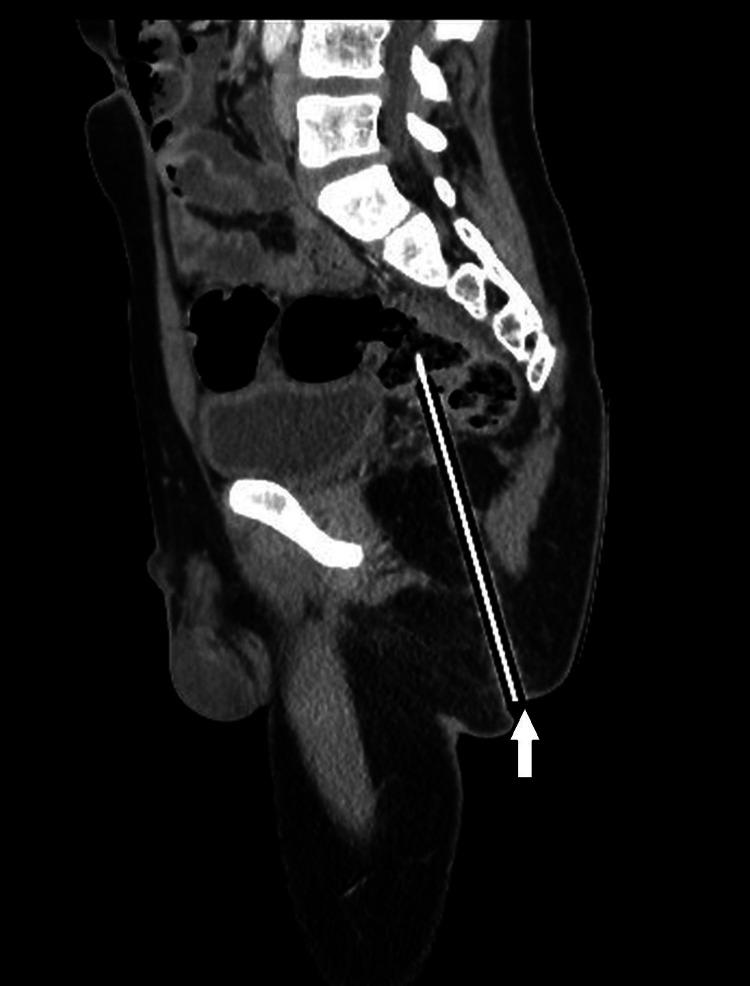

Pensel termasuk ke dalam gluteal sejauh 12.4cm

Walaupun nampak seperti tidak kritikal secara luaran, sebenarnya objek berkenaan telah menembusi daging punggung (gluteal) murid berkenaan sedalam 12.4cm. Imbasan seterusnya turut mengesahkan hujung pensel terbabit sudah terkena pada bahagian rektum (bahagian akhir usus besar).